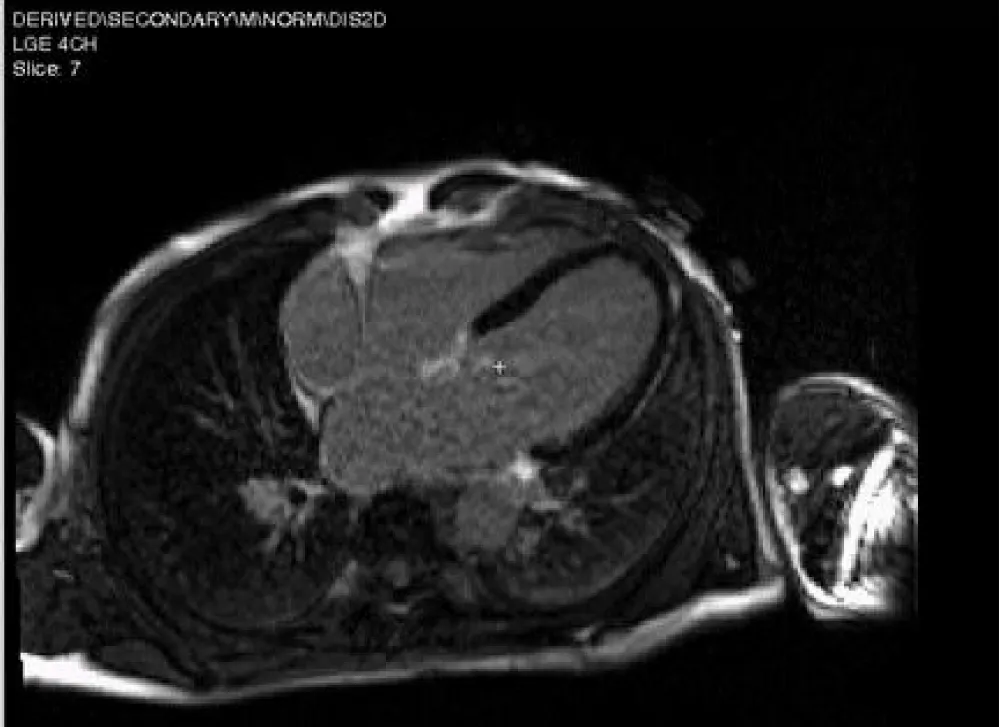

Figure 4: CMR-LGE 4 chamber view revealed no fibrosis.

Figure 5: Feature tracking of LV revealed mildly impaired GLS = -17.7%. Primary mitral regurgitation.

Figure 10: CMR -LGE, 3 chamber view revealed nonterritorial sub-endocardial fibrosis of lateral wall (arrows).

Figure 11: Feature tracking revealed impaired GLS = -13.1%.